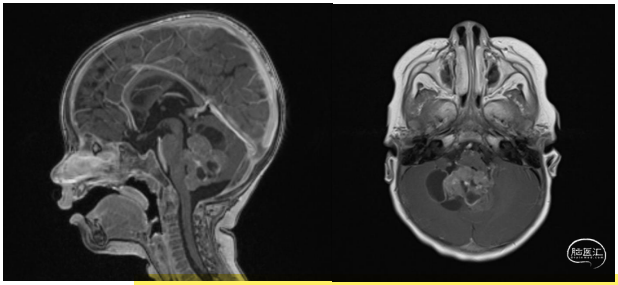

脑脊髓MRI成像示,后颅窝一异质性囊性出血性病灶,部分钙化,体积46×34×49毫米,阻塞第四脑室和右侧Luschka孔(图2)。